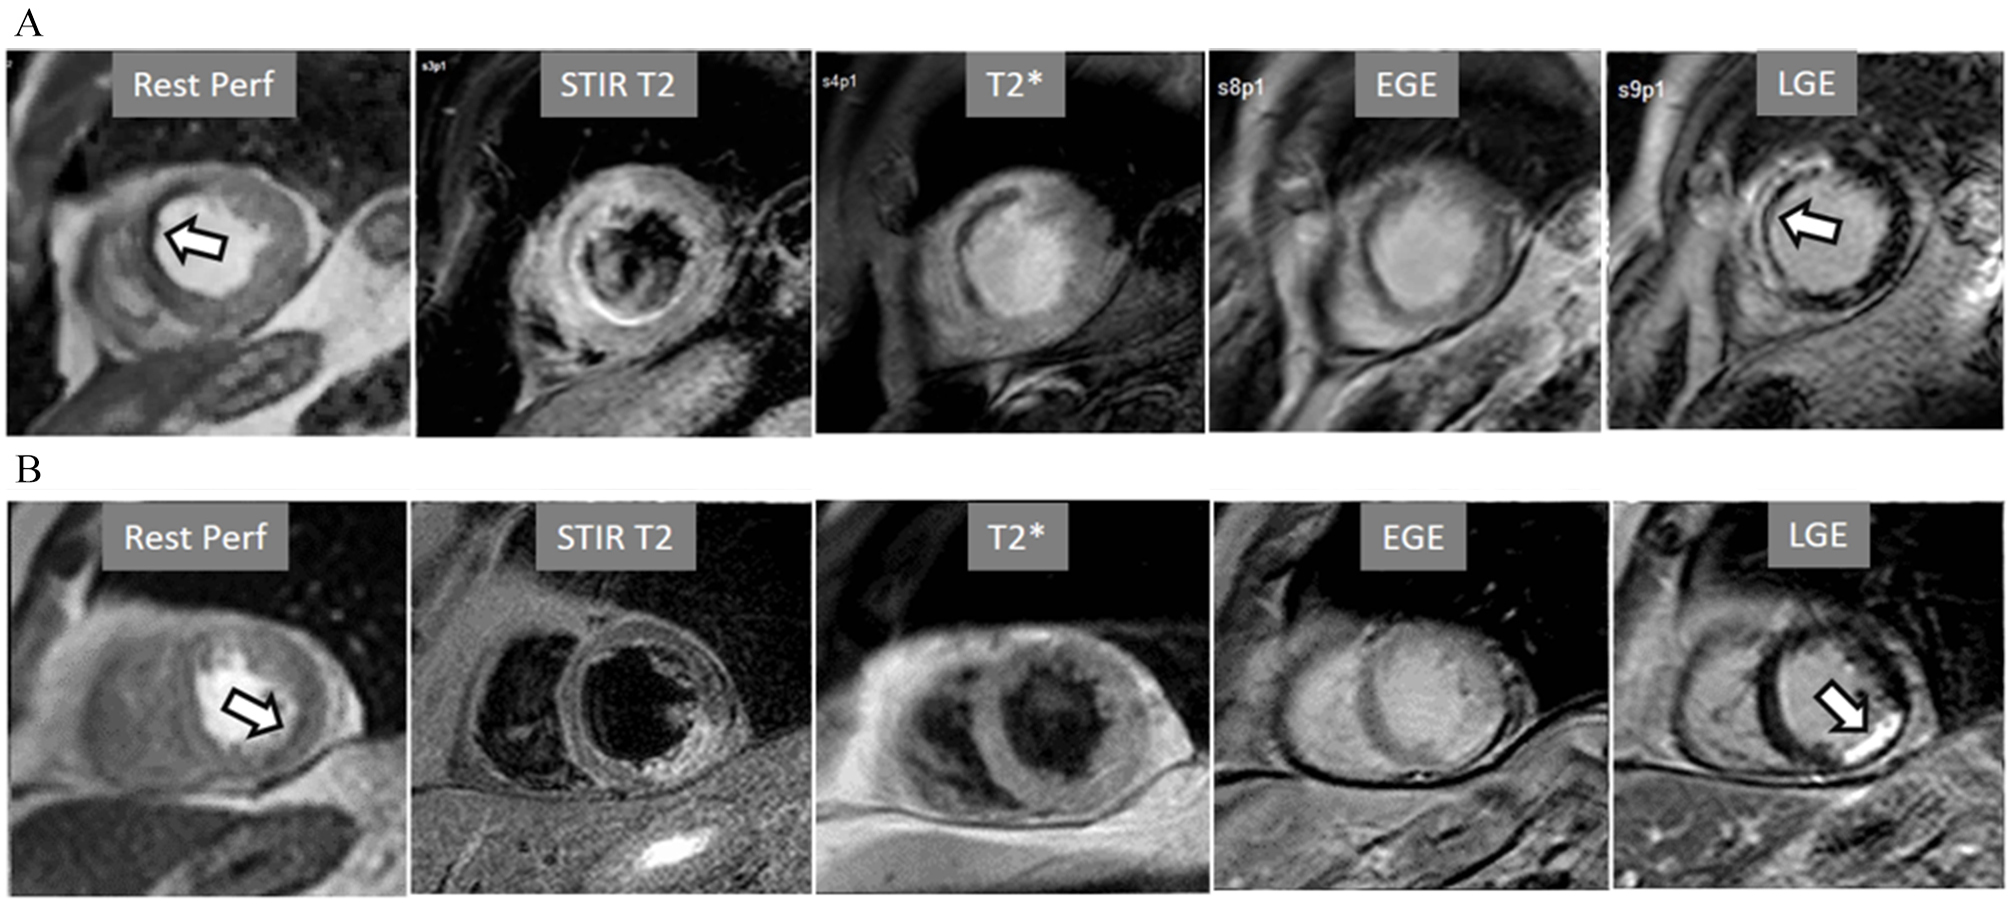

Particularly important, in practice, is the issue of perfusion studies in patients with previous MI. In theory, a basal rest perfusion study should exhibit a reduced signal intensity in the infarcted area, as is the case in the acute phase of a large transmural MI (Fig. 14A). However, not infrequently, the presence and extent of a rest perfusion defect does no correlate with the actual area of necrosis in either, acute (Fig. 14B) or chronic MI (Fig. 15). Signal intensity in areas of previous MI is thus, not dependent merely on the presence of scar tissue, but some other factors lead to differences in CA concentration between MI and remote regions and, in this sense, rest perfusion CMR cannot be equated to SPECT studies, where rest defects are directly related to the presence of infarcted myocardial tissue not amenable to radiotracer uptake [45].

Fig. 14.Rest perfusion after acute myocardial infarction. (A) Frames from different sequences in a case of acute MI showing, from left to right, (1) gross transmural defect at the rest perfusion study (arrow); (2) signs of regional myocardial edema at STIR T2, with a mid-line low intensity region which proves to be due to (3) intramural hematoma at T2* sequence; (4) persistence of hypoperfusion at Early Gadolinium Enhancement (EGE); and (5) transmural anteroseptal necrosis with a subendocardial area of microvascular obstruction (arrow). (B) The same series of sequences in another patient with AMI showing (1) mild subendocardial defect at rest (arrow); (2) regional edema; (3) absence of hematoma at T2*; (4) lack of persistent defect at EGE; and, finally, (5) a transmural infero-lateral LGE (arrow) without microvascular obstruction.